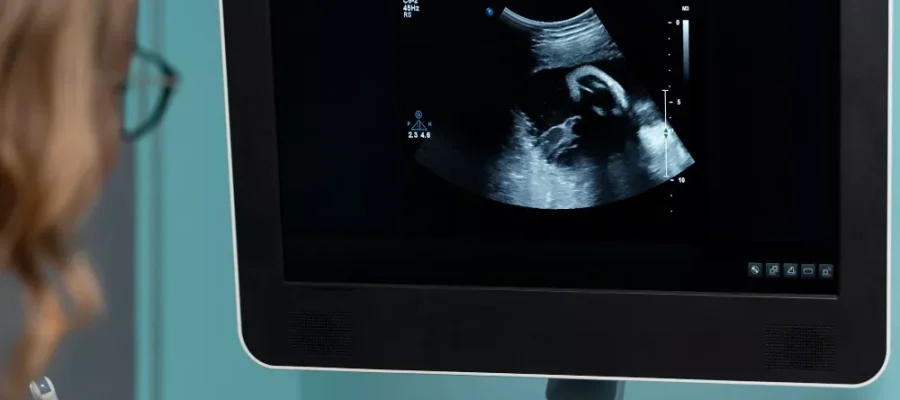

Gebelikte yapılan ultrason incelemesinde annede veya bebekte herhangi bir normal olmayan bulgu tespit edildiğinde daha ileri ve daha detaylı bir inceleme yapmak amacıyla kullanılmaktadır. Fetal MR incelemesi bebek için yapılabildiği gibi, gebelik döneminde anneye ait problemleri aydınlatmak için de güvenle kullanılabilir

Ultrason ses dalgası kullanarak görüntü elde eder, Fatal MR ise manyetik alanda görüntü elde eder. Gerek ultrason, gerekse fatal MR tetkikleri radyasyon içermez.